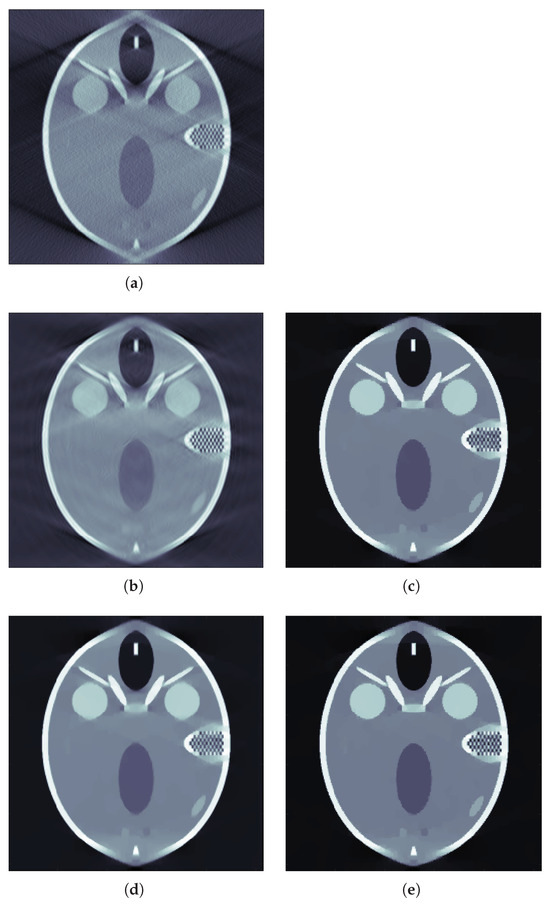

4.2. Results for Limited View Data

4.3. Results for Sparse View Data